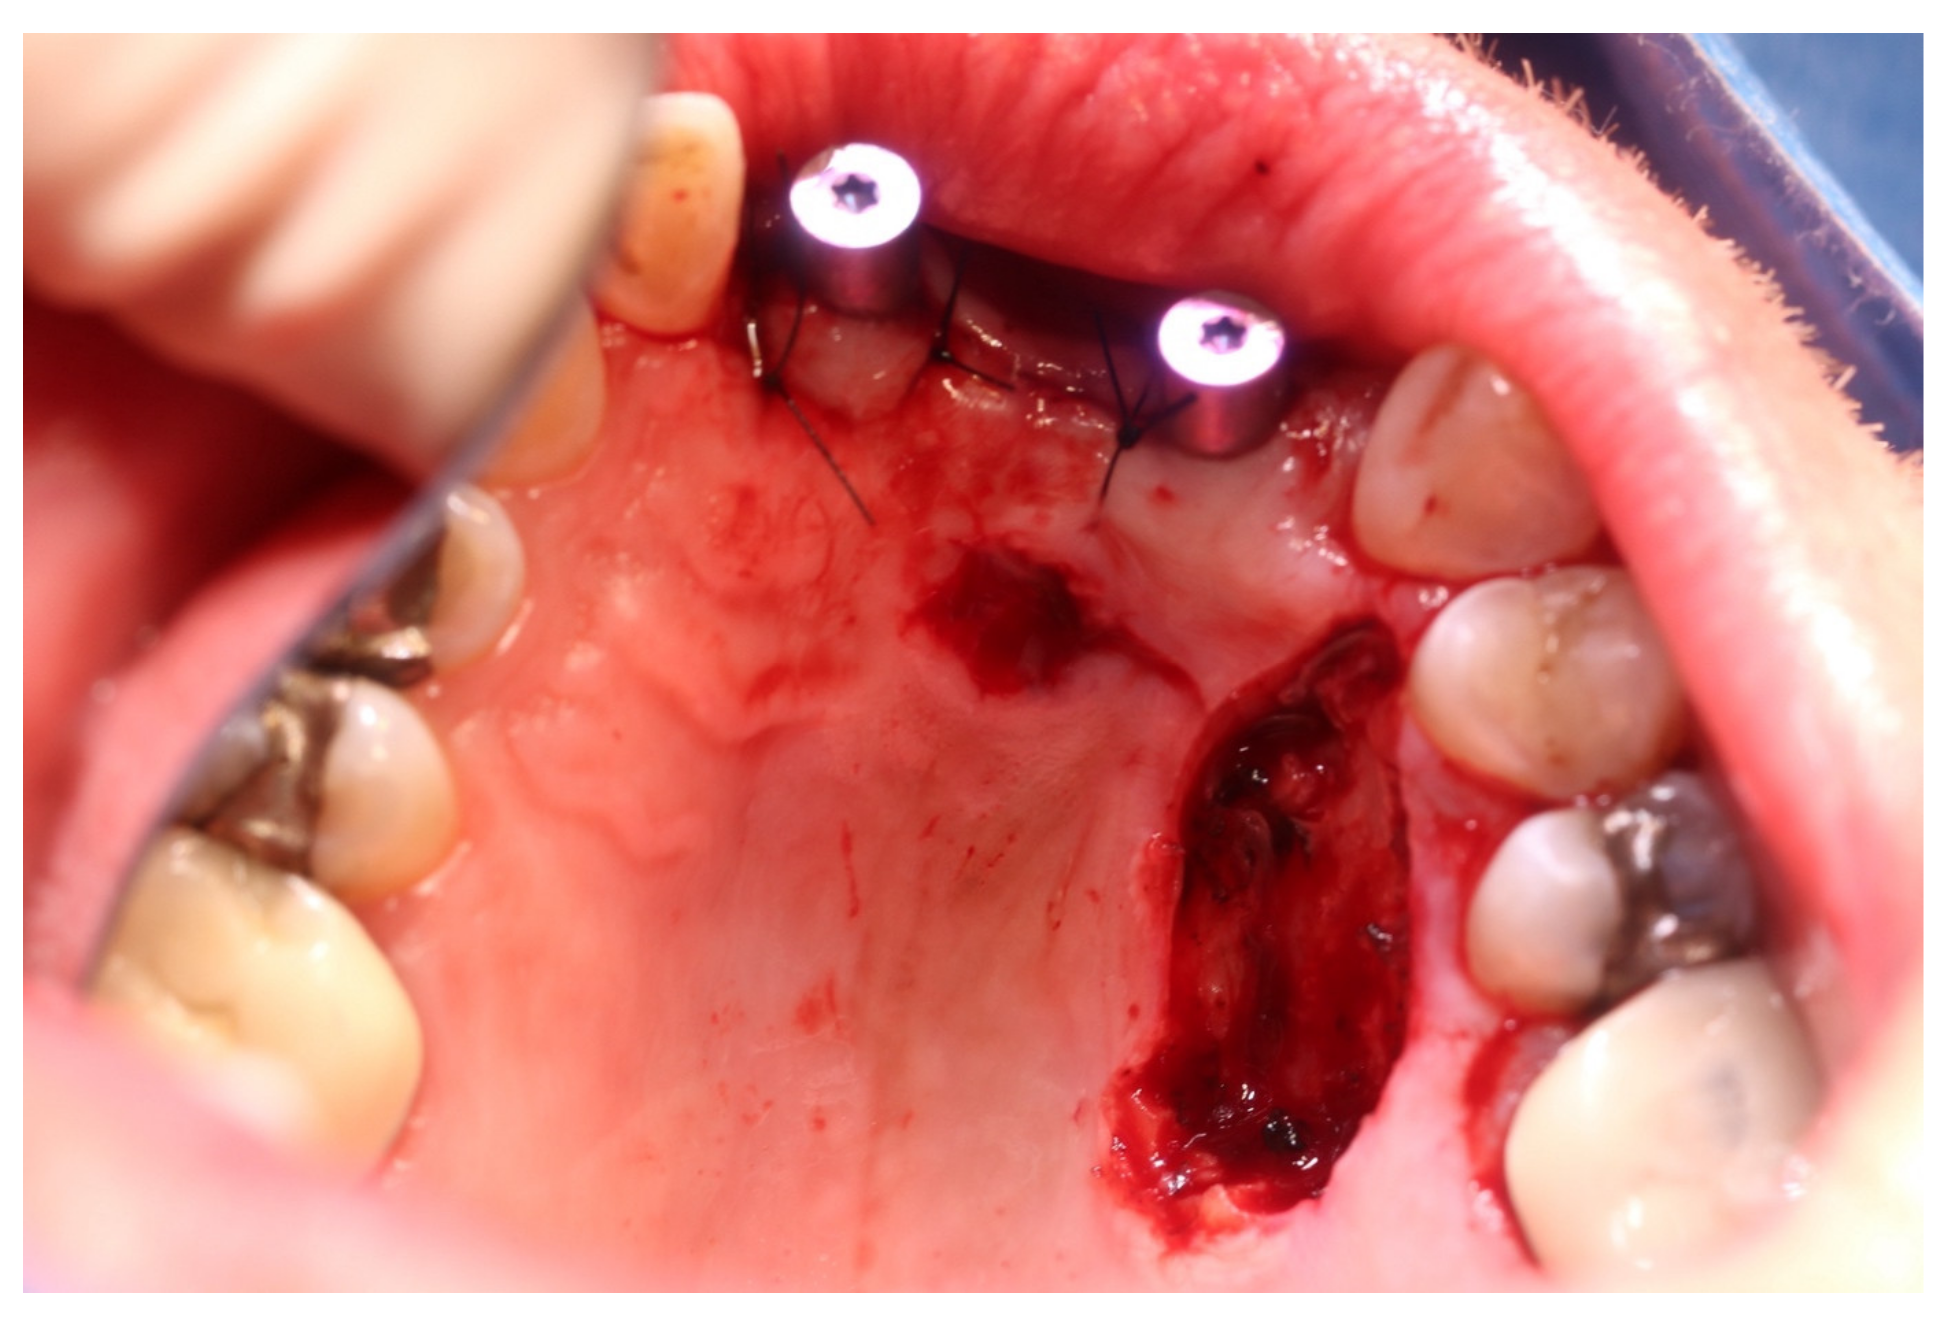

2. Case Report